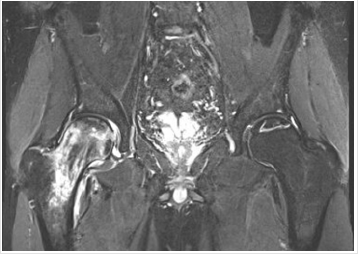

Patient had guarding and pain with movement. Of note, Log roll, FABER and FADIR tests were positive on the right hip. Left hip had slight limitation of movement. Bilateral hip x-rays showed degenerative changes of both hips with subchondral sclerosis with no acute ossific abnormality (Figure 2). MRI imaging of both hips demonstrated AVN without collapse or superimposed fracture or significant effusion or significant marrow edema on the left side (Figure 3). However, intense marrow edema throughout the right femoral head and neck suggested superimposed subcortical fracture on the right side with only minimal deformity of the articular surface. The patient underwent punch biopsy of the left lower extremity purpura; microscopic examination showed numerous extravasated erythrocytes associated with perivascular neutrophils and focal leukocytoclasia in the superficial dermis, consistent with leukocytoclastic vasculitis. Direct immunofluorescence examination was negative for IgM and IgG. However, it showed granular deposition of IgA and C3 within the walls of few superficial dermal vessels. These findings are consistent with IgA Vasculitis. Blood workup included the following: CBC revealed WBC of 7.6 X10E9/L, Hemoglobin of 15.5g/dL, and Platelets of 149 X10E9/L.

Figure 3: Coronal MRI of the bilateral hip showing evidence for bilateral AVN. There is some bright T2 signal surrounding the infarct at the top of the left femoral head without significant edema to suggest collapse, fragmentation or fracture.